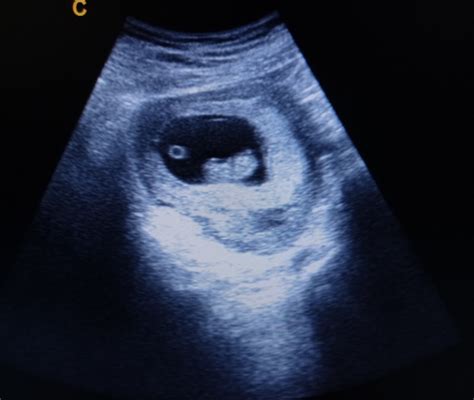

Durante questa ecografia precoce, è possibile osservare diverse strutture che confermano l'avvenuta gravidanza:

1. Sacco Gestazionale

È la prima struttura visibile, solitamente identificata già nelle prime settimane. Appare come un'immagine scura, di forma circolare o ovale, circondata da un alone biancastro (ecorefringente), situata all'interno dell'endometrio, lo strato interno dell'utero che si è ispessito per accogliere l'embrione.

2. Vescicola Vitellina

Questa struttura appare poco dopo il sacco gestazionale ed è fondamentale per il nutrimento e lo sviluppo iniziale dell'embrione. La sua forma circolare e il colore bianco alla ecografia possono ricordare i follicoli osservati durante la stimolazione ovarica.

3. Battito Cardiaco

A partire dalla sesta settimana di gestazione, è solitamente possibile apprezzare il battito cardiaco dell'embrione. La sua rilevazione è un segno rassicurante di vitalità.

4. L’ Embrione

L'embrione è costituito da una massa di cellule embrionarie che daranno origine a tutti gli organi e tessuti del futuro bambino. Appare come una piccola struttura adesa alla vescicola vitellina. Nella sesta settimana, la sua dimensione può variare (spesso tra 2-8 mm) e cresce rapidamente, circa 1 mm al giorno. La sua visualizzazione e misurazione precisa sono indicatori chiave dello stato di avanzamento della gravidanza.